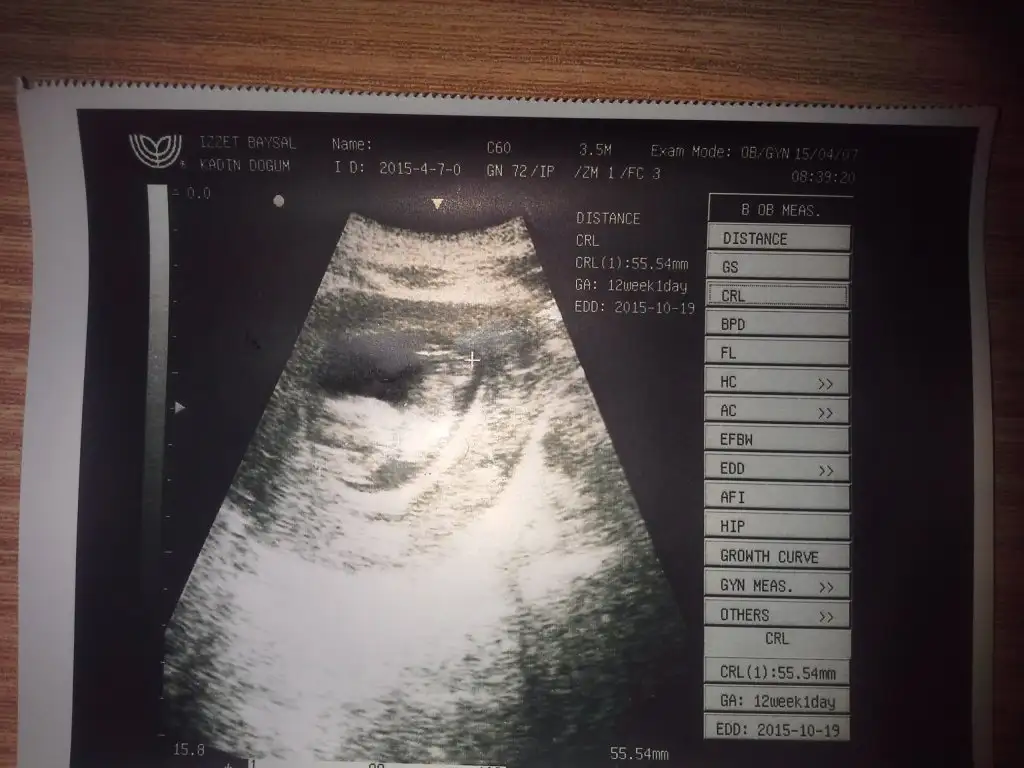

KizKızlar buda benim bebişim 12 haftalık bugün gittim.Dktr. sizce fikre olan varsa yazabilirmi lütfen.

Doktor tahminde bulunmadimi canim ilkbresimde kesin kiz gibi...Kızlar buda benim bebişim 12 haftalık bugün gittim.Dktr. sizce fikre olan varsa yazabilirmi lütfen.

Canım seninde bir oğlun varmış ama ben bunu erkeğe benzettim. En güzeli Allah bilir :)Kızlar buda benim bebişim 12 haftalık bugün gittim.Dktr. sizce fikre olan varsa yazabilirmi lütfen.